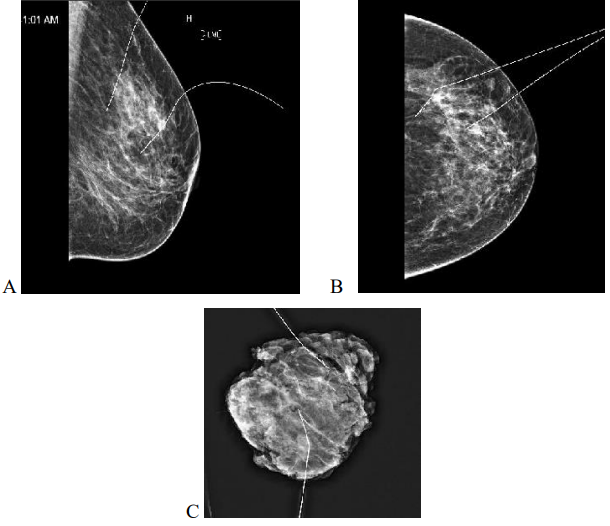

Directly after the procedure, cranio-caudal (CC) and medio-lateral (ML) mammograms were obtained to confirm accurate placement (Figure 1). Skin marking with a permanent pen was also done to indicate site and depth of lesion if the localization was performed on the day of surgery to aid the site of surgical excision. In most cases the localization was done to bracket the extreme ends of the lesion either medial and lateral or superior and inferior.

Figure 3: 63yr old with 24 BMI, Bra size 36 DD with invasive carcinoma measuring 66 mm on pre op imaging, post op specimen weighed 129gm, tumerectomy and partial breast reconstruction with chest wall perforator flap. Margins clear. Mediolateral (A) and Craniocaudal (B) mammograms showing two RFID tags marking the medial and lateral extent of disease with specimen X rays shows radiologically clear margins (C,D)